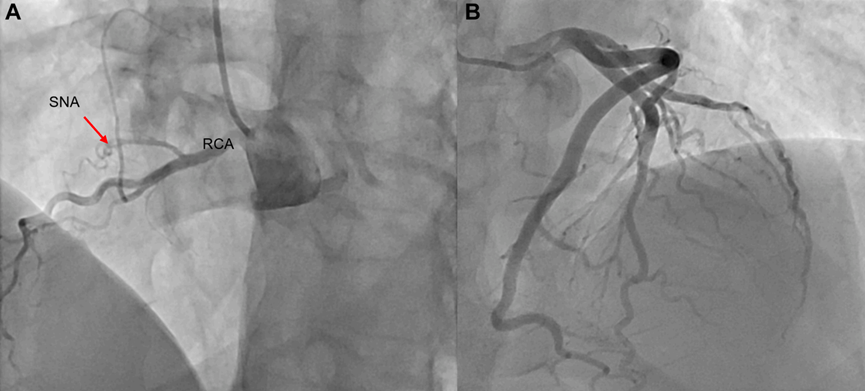

随后数周内,患者心绞痛发作愈发频繁且加重,运动耐受能力逐渐下降,最终不得不停止一切竞技训练。遂为其安排了有创

图4

病例再次经心脏多学科团队讨论后一致决定,尽管患者异常右冠为非优势血管,但其临床症状和生理检测均提示存在明确的心肌缺血证据,表现为窦房结功能障碍。据此,为患者施行了单支右侧乳内动脉到右冠状动脉锐缘支的冠状动脉旁路移植术。